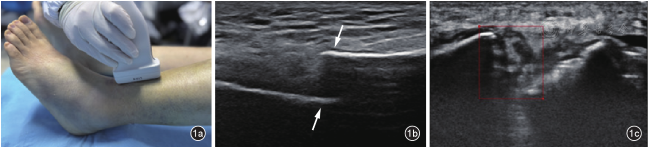

检查由一名具有10年以上超声工作经验的资深超声医师操作。根据解剖部位及患肢肿胀情况选择探头,调节仪器参数(深度、增益、聚焦等),深度一般设置为2~5 cm,增益调节至适中,聚焦放置于骨表面,以确保骨折断端及周围软组织成像质量最佳。超声探头平行于长骨纵轴并垂直于骨表面(图1a),采集清晰的骨折断端图像(图1b),每例患者采集5~8张,并保存为JPG格式。构建超声影像数据库,内容包括患者基本信息,如年龄、性别、骨折时间、骨折原因、骨折部位等,以及相关超声影像资料。

图1 骨折超声影像数据的采集及断端标注。图a为纵切面超声图像采集操作示意图,超声探头置于肢体骨折处,垂直骨表面;图b为超声长轴切面图像,箭头所示为胫骨骨折断端;图c为使用Labelme软件进行肢体长骨骨折断端超声图像的矩形框标注,矩形框完整地包绕断端